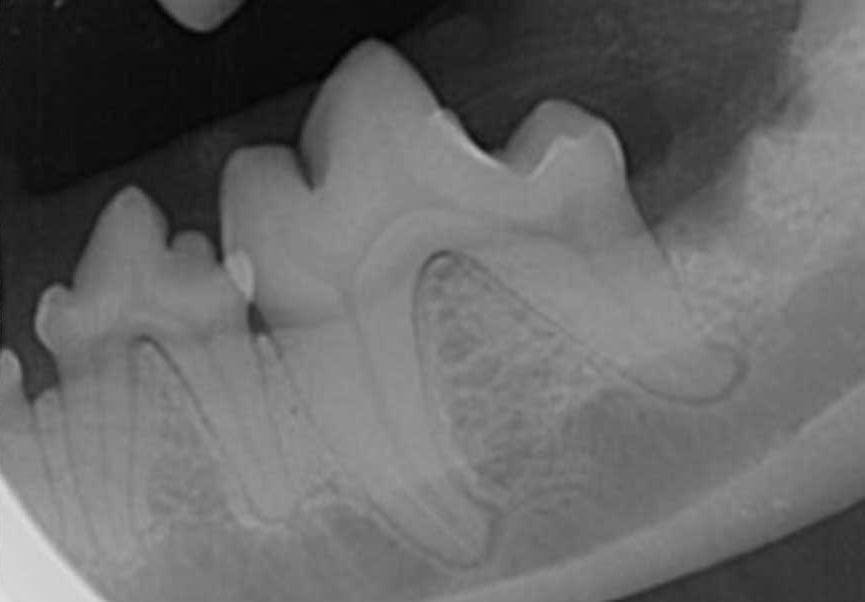

Figure 4. Dental radiographs of left and right mandibular first molar teeth in a five-year-old dog with moderate periodontal disease. The mandibular second molar teeth were extracted and open root planing performed on the distal aspect of the distal roots of the first molar teeth. The owner was very motivated to salvage the teeth and committed to twice-daily brushing.